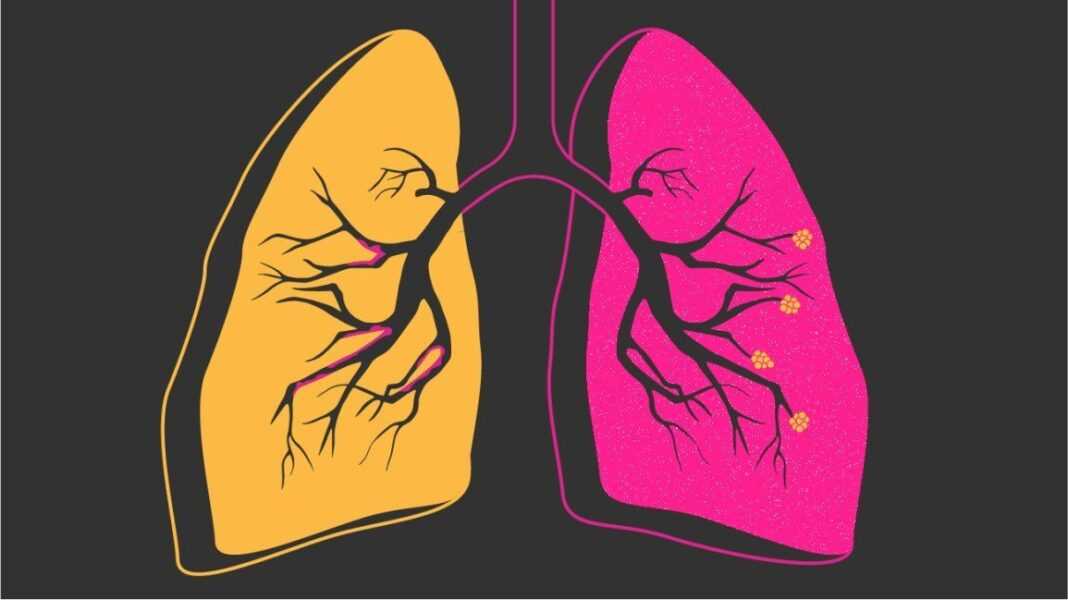

Η ΧΑΠ αποτελεί μία χρόνια φλεγμονώδη νόσο των αεραγωγών και των πνευμόνων, που τελικά καταλήγει να επηρεάζει τη λειτουργία ολόκληρου του σώματος. Τρείς είναι οι βασικότερες αιτίες της νόσου, που οδηγούν στην κακή θρέψη και τελικά στην απώλεια κιλών: